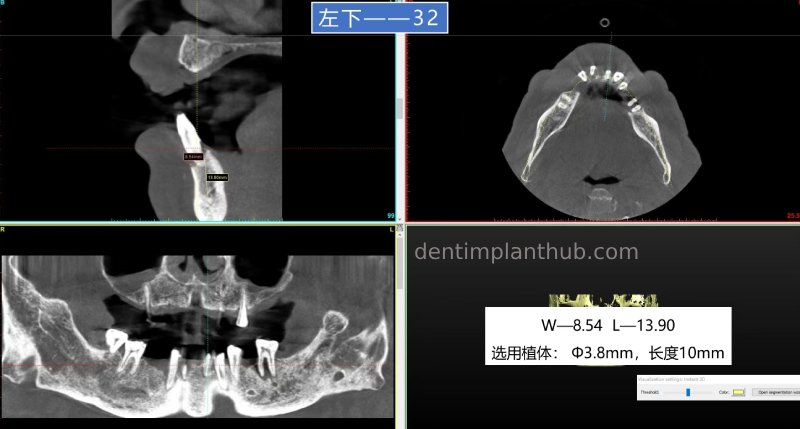

42, 32, immediate extraction and implantation, follow-up restoration together with continuous crowns;

32, ready-to-use implant, implant model 3810;